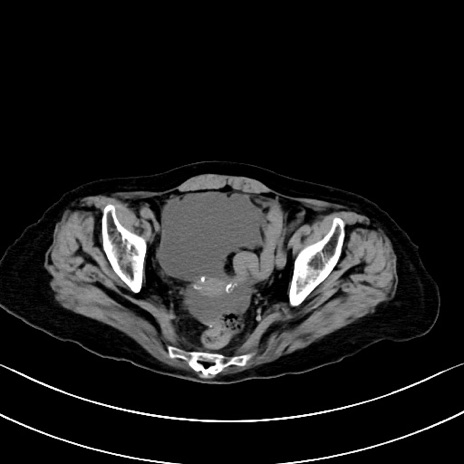

横断像